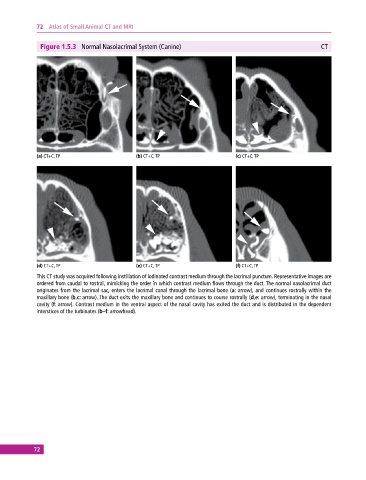

Figure 1.5.3 Normal Nasolacrimal System (Canine) CT

(a) CT+C, TP (b) CT+C, TP (c) CT+C, TP

(d) CT+C, TP (e) CT+C, TP (f) CT+C, TP

This CT study was acquired following instillation of iodinated contrast medium through the lacrimal punctum. Representative images are

ordered from caudal to rostral, mimicking the order in which contrast medium flows through the duct. The normal nasolacrimal duct

originates from the lacrimal sac, enters the lacrimal canal through the lacrimal bone (a: arrow), and continues rostrally within the

maxillary bone (b,c: arrow). The duct exits the maxillary bone and continues to course rostrally (d,e: arrow), terminating in the nasal

cavity (f: arrow). Contrast medium in the ventral aspect of the nasal cavity has exited the duct and is distributed in the dependent

interstices of the turbinates (b–f: arrowhead).